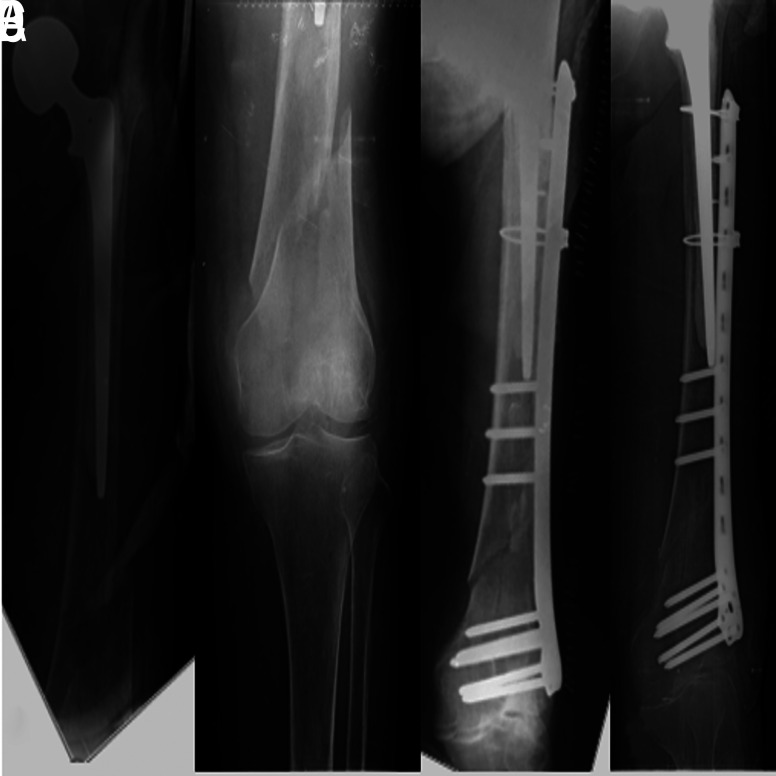

本研究旨在调查一家三级转诊中心连续收治的一组温哥华B1型和C型股骨假体周围骨折(PPF)患者中,使用混合锁定钢板/钢缆技术进行切开复位内固定术(ORIF)治疗的中长期手术效果。研究纳入了2005年至2016年期间诊断为温哥华B1型或C型股骨假体周围骨折并采用混合锁定钢板/钢缆技术治疗的25名患者(25例PPF;17名女性,8名男性)。根据患者最终随访时的哈里斯髋关节评分(Harris Hip Score,HHS),将患者的功能状态分为四组:70=效果差;70-80=一般;80-90=良好;90-100=优秀。术中和术后并发症也被记录在案。PPF愈合的临床定义是患者能够在有人或无人协助的情况下承受全部重量,X光片上的定义是出现与骨折桥接的胼胝。根据温哥华分类和HHS固定类型以及愈合时间进行了分组分析。初次髋关节置换时的平均年龄为 57 ± 16.6(17-82 岁)岁,PPF 时的平均年龄为 64 ± 18.7(24-88 岁)岁。从初次手术到PPF的平均随访时间为5.6±3.3(范围,2-14)年,PPF后的平均随访时间为6.5±4.1(范围,3-15)年。其中有 7 例 B1 型 PPF 和 18 例 C 型 PPF。在最后的随访中,平均 HHS 为 71 ± 7.74(范围为 57-89)。根据 HHS,8 名患者的功能效果较差,14 名患者的效果一般,3 名患者的效果良好。术中和术后均未发现重大并发症。所有患者平均在 13 ± 4.9 周(6-24 周)内实现骨折愈合,无并发症发生。在亚组分析中,虽然HHS没有观察到显著差异(温哥华类型的P=.87,固定类型的P=.96),但各组的骨折愈合时间不同。B1 型 PPF 的接合时间明显短于 C 型 PPF(P=.006)。与骨水泥固定组相比,非骨水泥固定组的骨结合时间要短得多(P=.017)。在锁定钢板上添加钢索可提供足够的稳定性,以保持骨折对位,实现温哥华B1型和C型PPF的骨性结合。虽然此类患者可通过ORIF实现骨结合,但在使用骨水泥股骨干或温哥华C型PPF的情况下,可能需要更长的骨结合时间。

This study aimed to investigate the mid-to-long-term surgical outcomes of open reduction and internal fixation (ORIF) using a hybrid locking plate/cable technique for the treatment of Vancouver type B1 and type C periprosthetic femoral fractures (PPFs) in a consecutive group of patients from a single tertiary referral center. Twenty-five patients (25 PPFs; 17 female, 8 male) in whom a Vancouver type B1 or type C PPF was diagnosed and treated by a hybrid locking plate/cable technique from 2005 to 2016 were included in the study. Patients' functional status was categorized into 4 groups based on the Harris Hip Score (HHS) at the final follow-up: 70=poor result; 70-80=fair; 80-90=good, and 90-100=excellent. Intraand postoperative complications were also recorded. PPF union was defined clinically as the patient's ability to bear full weight with or without assistance and radiographically as the presence of a callus bridging the fracture. Subgroup analyses were conducted according to the Vancouver classification and type of fixation regarding the HHS and time to union. The mean age was 57 ± 16.6 (range, 17-82) years at the time of the primary hip replacement and 64 ± 18.7 (range, 24-88) years at the time of PPF. The mean follow-up was 5.6 ± 3.3 (range, 2-14) years from primary procedure to PPF and 6.5 ± 4.1 (range, 3-15) years following PPF. There were 7 type B1 and 18 type C PPFs. At the final follow-up, the mean HHS was 71 ± 7.74 (range, 57-89). According to HHS, functional results were poor in 8 patients, fair in 14 patients, and good in 3 patients. No major intra- or postoperative complications were noted. Fracture union was achieved in all patients without complications at an average of 13 ± 4.9 (range, 6-24) weeks. In subgroup analysis, while no significant differences were observed in the HHS (P=.87 for the Vancouver type, P=.96 for the type of fixation), time to union differed among groups. Time to union was significantly shorter in type B1 than in type C PPFs (P=.006). Time to union was considerably shorter in the uncemented group compared to the cemented one (P=.017). Adding cables to the locking plate can provide adequate stability to preserve fracture alignment and achieve bony union in Vancouver type B1 and C PPFs. Although union can be achieved by ORIF in such patients, a longer union time may be required for PPFs in the setting of a cemented femoral stem or Vancouver type C. Level IV, Therapeutic study.